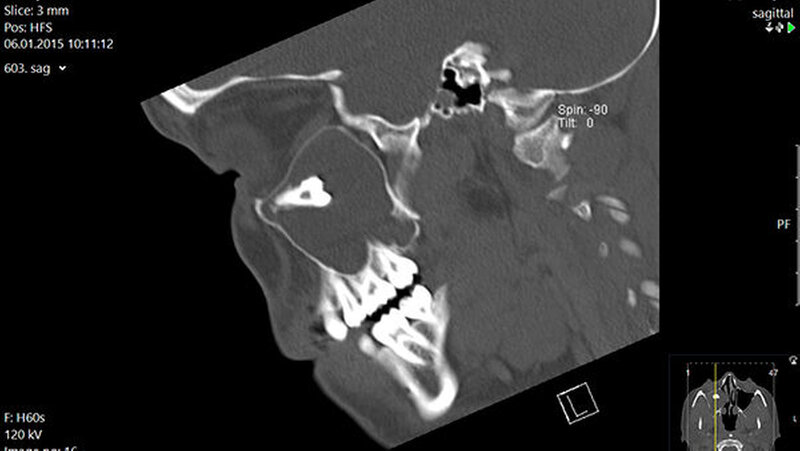

In der regionalen Klinik (Winterberg-Krankenhaus Saarbrücken) wurde zusätzlich eine kontrastmittelunterstützte Computertomografie der Nasennebenhöhlen durchgeführt (Abbildungen 2 und 3), die den Befund bestätigte und präzisierte.